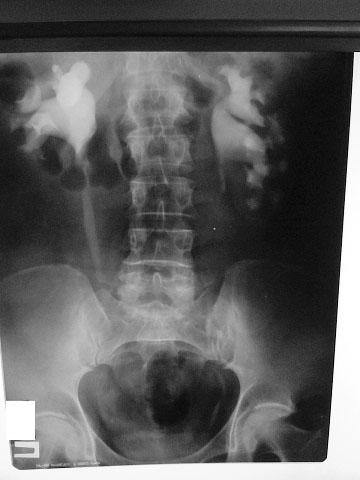

Рентгенолог сказал, что есть сдавление правого мочеточника извне на уровне с\3. Снимки не видела. Думаю, после обеда смогу их увидеть и выложить. Хочу её после обеда, как освободится аппарат, пересмотреть.

L3 ?Anastasia писал(а):Рентгенолог сказал, что есть сдавление правого мочеточника извне на уровне с\3. Снимки не видела. Думаю, после обеда смогу их увидеть и выложить. Хочу её после обеда, как освободится аппарат, пересмотреть.

средней трети мочеточника

Сори за задержку- технические трудности.

Вот снимки:

По УЗИ получается что эта штука должна быть примерно здесь - указано стрелкой - или чуть ниже.

Еще желательно проинспектировать нижнюю треть правого мочеточника при наполненном мочевом пузыре - непонятна атония мочеточника на всем протяжении, нужно искать причину.